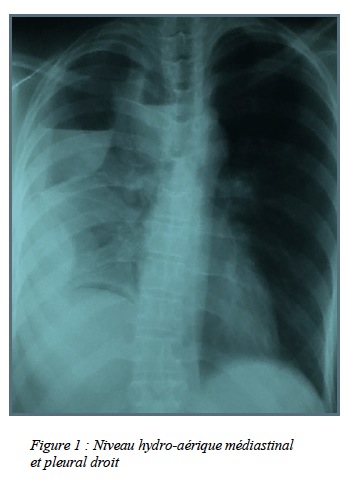

pneumopathie d’inhalation soit à un pneumothorax par brèche pleurale lors de la laparoscopie. Nous avions décidé de réaliser une radiographie pulmonaire examen plus accessible avant d’envisager une fibroscopie des voies aériennes. La radiographie pulmonaire avait permis de mettre en évidence un hydropneumothorax droit de grande abondance (figure 1)

ce qui avait motivé la mise en place d’un drainage thoracique. Devant l’absence de production du drain, une tomodensitométrie (TDM) thoracique avait été réalisée et avait permis de mettre en évidence la persistance de l’épanchement hydroaérique pleural droit associé à un épanchement hydoaérique paramédiastinal du même côté. Cette tomodensitométrie avait bien individualisé le drain posé au paravent qui était par ailleurs exclu, et avait permis d’éliminer l’existence d’une fistule broncho-pleurale. Par contre, il y avait un doute quant à l’intégrité de l’oesophage (figure 2)